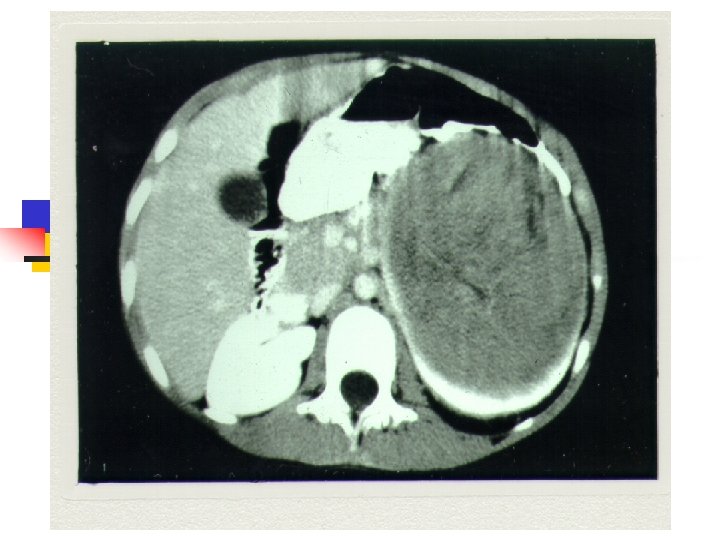

Diagnostic evaluation n n n History and physical Urinalysis Renal function tests Chemistries Abdominal USD Chest x-ray Abd/Chest CT